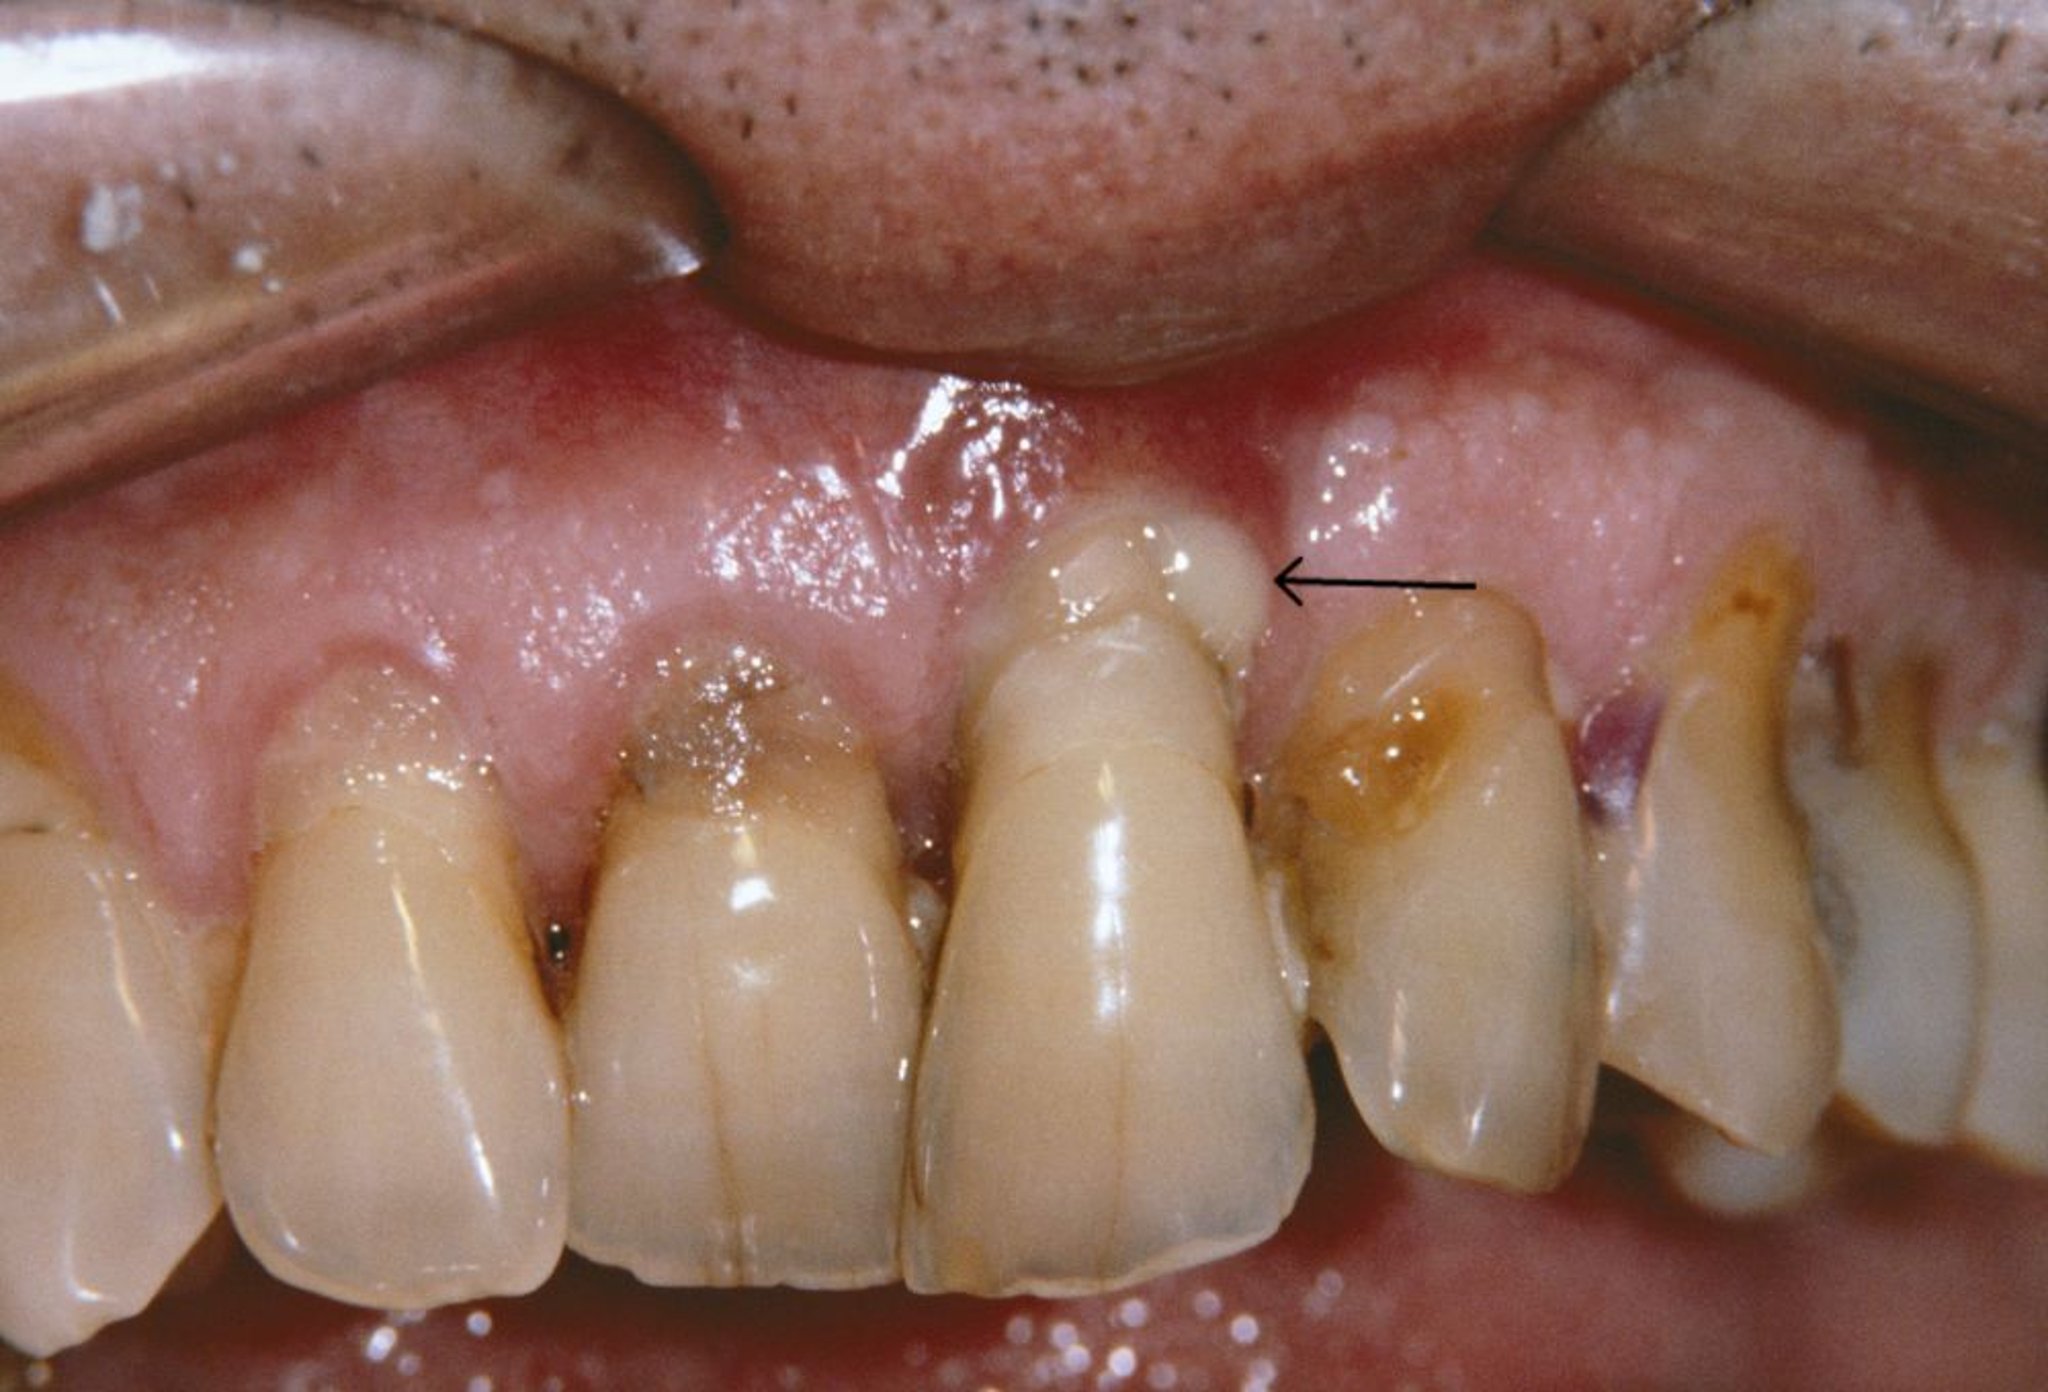

Esta fotografía muestra retracción de las encías y un absceso periodontal (flecha) en una persona que tiene periodontitis.